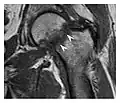

The greater tuberosity of the humerus is also an illustrative location of occult fractures. The osseous injury may follow seizures, glenohumeral dislocation, forced abduction, or direct impaction. They are commonly discovered on MRI in symptomatic patients with suspicion of rotator cuff tear. Coronal images are best suited for detection. They appear as crescentic oblique lines surrounded by a bone marrow edema pattern (Figure 5). The rotator cuff must be inspected since associated ligamentous lesions are common. In the ankle, malleoli and tarsal bones should be checked carefully for any cortical disruptions and radiolucent lines that may reveal a fracture. Awareness of the exact location of the pain will help direct the attention of the interpreter when searching for very subtle signs of fracture (Figure 6).[1]

a

b

Figure 13: Partial osseous avulsion of the gluteal muscles at the greater trochanter in a 59-year-old man who presented with the right hip pain without a history of trauma. Lauenstein view and anteroposterior and radiographs (not shown) did not show an obvious fracture line or disruption of bony contours in the acetabulum or the right femoral neck. (a) Coronal T1-weighted MRI displays an incomplete fracture line extending partially from the greater trochanter (arrow). (b) Coronal short tau inversion recovery MRI shows heterogeneous hyperintensity in the same region (arrow) as well as hyperintensity within the gluteus medius and minimus muscles (arrowheads) consistent with tissue edema and hematoma.[1]